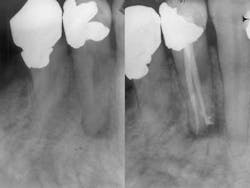

With thermoplastic obturation in its several forms and cold lateral and vertical condensation producing voids and the potential for excess stresses to the roots, my choice for trauma-free obturation is a single-point technique. It is a passive technique that will not generate excessive stresses. The question asked by those using alternate techniques is whether or not it is an effective means for canal obturation. Like all obturation systems, the effectiveness of the single-point technique is based on the cement. However, the single-point technique requires that the cement be an effective seal in both thick and thin layers and that it be present in sufficient quantity that it can fill all the gaps between the master gutta-percha cone and the walls of the canal. For this to happen, we need an instrument that can flood the canal with cement prior to the placement of the prefitted gutta-percha point.

One last question that someone might ask is what do we do when the canals are highly oval with a lot of buccal and lingual space after the master point has been placed? One can go two ways. The cement already flooding the canal is occupying that space effectively and needs no further gutta-percha points. Alternatively, one can use a spreader to create a lateral space for the placement of an auxiliary point with the proviso that the pressure applied to the spreader does not exceed the weight of one’s hand. We have no desire to mold the gutta-percha that would induce the rebound effect or expose the roots to any further stress. Rather, we apply just enough pressure to create a space where a subsequent well-coated point is then placed.

By using a passive obturation technique, we scrupulously avoid the introduction of stresses, maintain the accurate placement of the gutta-percha point, and avoid the introduction of voids that would compromise the seal. The fact that the employment of this technique is simpler and far less expensive is a wonderful marketing feature, but does not surpass the fact that it is safer and kinder to the tooth.